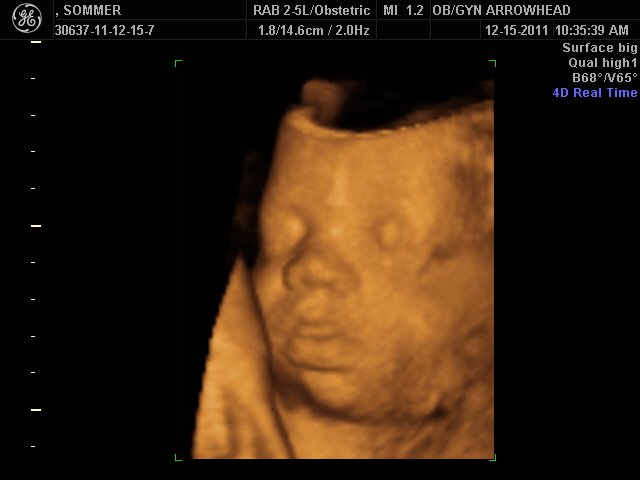

We offer complimentary 3D/4D Ultrasounds to all our OB patients around 30 weeks! The following photos are some examples of our work, shown with permission from our patients.